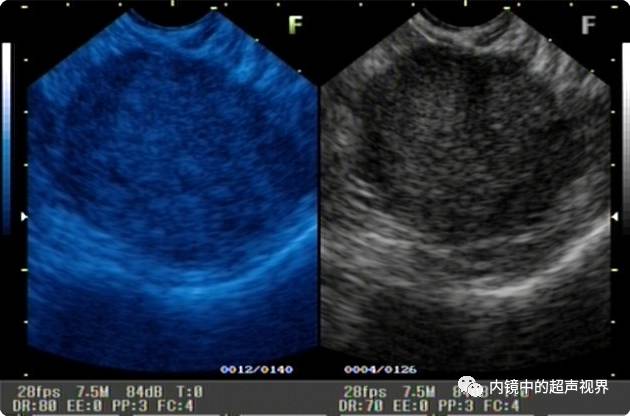

再来一纵隔肿物的图片,是DR30和80的对比,很明显。

纵隔肿物